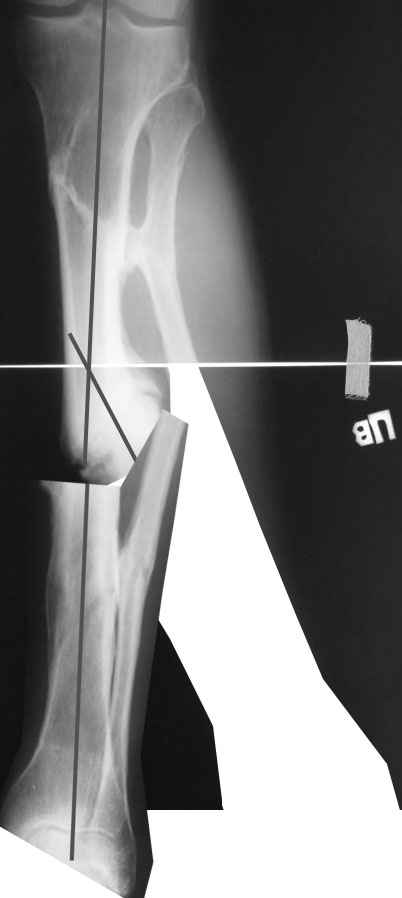

Мы бы сделали после остеотомии малоберцовой и аппаратной коррекции. Большеберцовую можно исправить за счет растяжения пседартроза. Можно и сделать поперечную остеотомию чуть дистальнее несращения, в этом случае будет удобный вход в периферический отломок. А зону несращения пройти разверткой просто по прямой. Схема в приложении.

Да все реально. Чтобы эти трудности уменьшить, лучше углы и ширину устранить с небольшой гиперкоррекцией, а главое - создать запас по длине.

Ткани сильно натянутся. И закрыто вывести дистальный отломок под гвоздь будет проблематично, даже если дистрактор наложить. Можно попытаться одномоментно сопоставить, но без фанатизма. Ели что не устраняется сразу, аппаратом за несколько дней дозированно уже

дотягиваем.